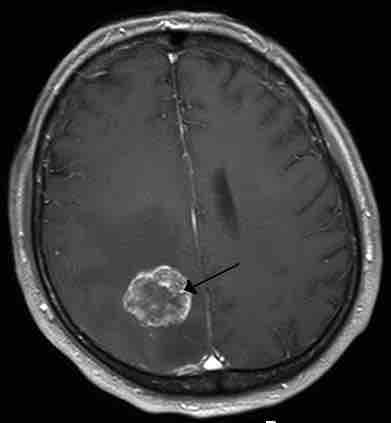

Metastasis in the Right Hemisphere

Brain metastasis in the right cerebral hemisphere from lung cancer shown on T1-weighted magnetic resonance imaging with intravenous contrast.